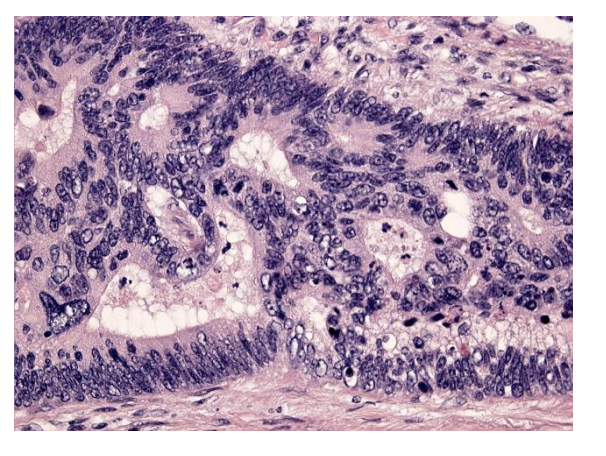

Hvilken diagnose svarer bedst til billedet?

a. Kronisk inflammation i hud

b. Planocellulært karcinom i hud

c. Tatoveringspigment i hud

d. Kulstøvsaflejring i hud

e. Malignt melanom i hud

*e. Malignt melanom i hud